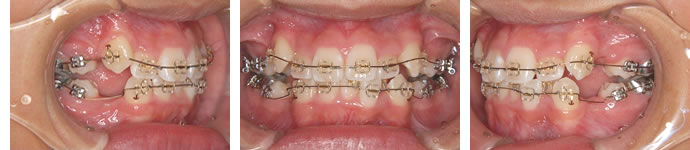

■装置装着 1ヶ月後

歯を並べるスペースを得るために上下左右の4番目を抜歯して、目立たない審美ブラケットを装着して治療を開始しました。

細いワイヤーを通し、まず歯の傾きやガタガタを取っていきます。

■装置装着 25ヶ月後

スペースも閉じてしまい、歯がだいたい並びました。これから咬み合わせをしっかりつくるために微調整をしています。歯の位置等をよくみて、ワイヤーに曲げを加えています。